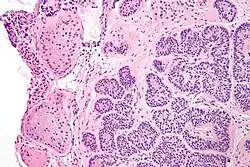

Micrograph of a Sertoli cell nodule. H&E stain. -

Micrograph of a Sertoli cell nodule. H&E stain.

Sertoli cell nodules are unencapsulated nodules that consist of:[2][3][4]

- cells arranged in well-formed tubules (that vaguely resemble immature Sertoli cells), with

- bland hyperchromatic oval/round nuclei that are stratified, and

- may contain eosinophilic (hyaline) blob in lumen (centre).